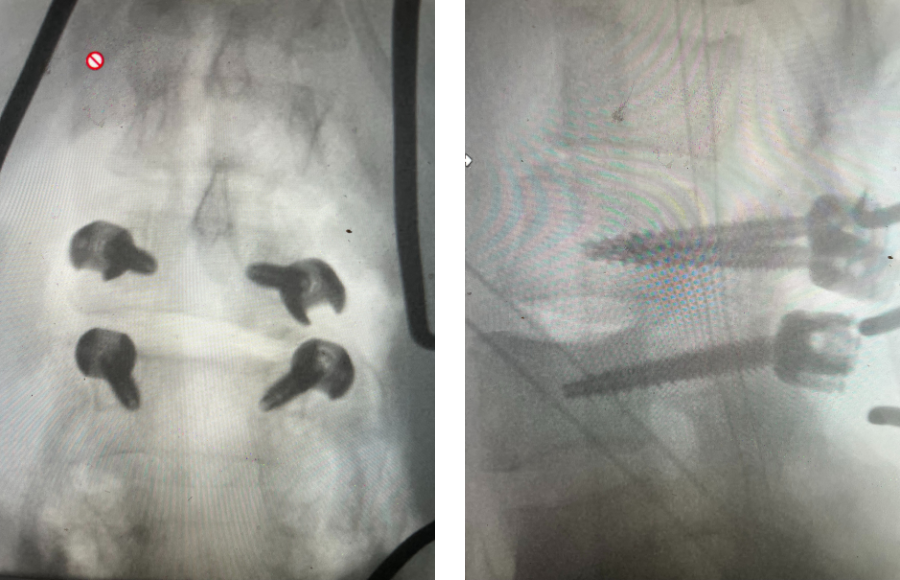

The actual structural cause of lumbar thecal sac compression can vary in degenerative spondylolisthesis and stenosis. The culprits are commonly thickened ligamentum flavum or severe facet […]